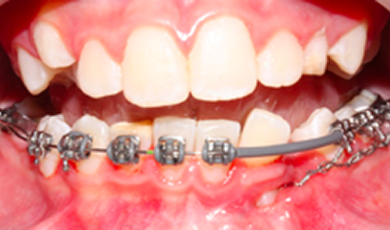

Início do tracionamento

Inicio do tracionamento ortodontico apos exposicao cirurgica ainda com a presenca de dentes deciduos, utilizando um arco lingual de apoio.